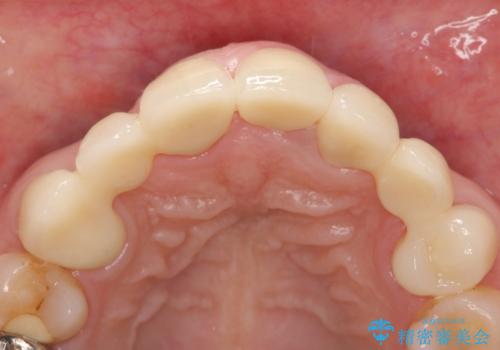

- 昔治療した前歯の被せ物の見た目を改善したいといらっしゃった方の症例です。

左上4番目の歯から右上3番目の歯まで計7歯のクラウンを除去し、オールセラミッククラウンによる補綴を行いました。

今回用いたオールセラミッククラウンはジルコニアフレームという白い素材の上にセラミックを盛っているため、審美性が非常に高いのが特徴です。

また、ジルコニアは人工ダイヤモンドの材料にも使われているほど高い強度を持っており、そのためオールセラミッククラウンは審美性だけでなく、奥歯やブリッジの補綴も可能とするクラウンです。